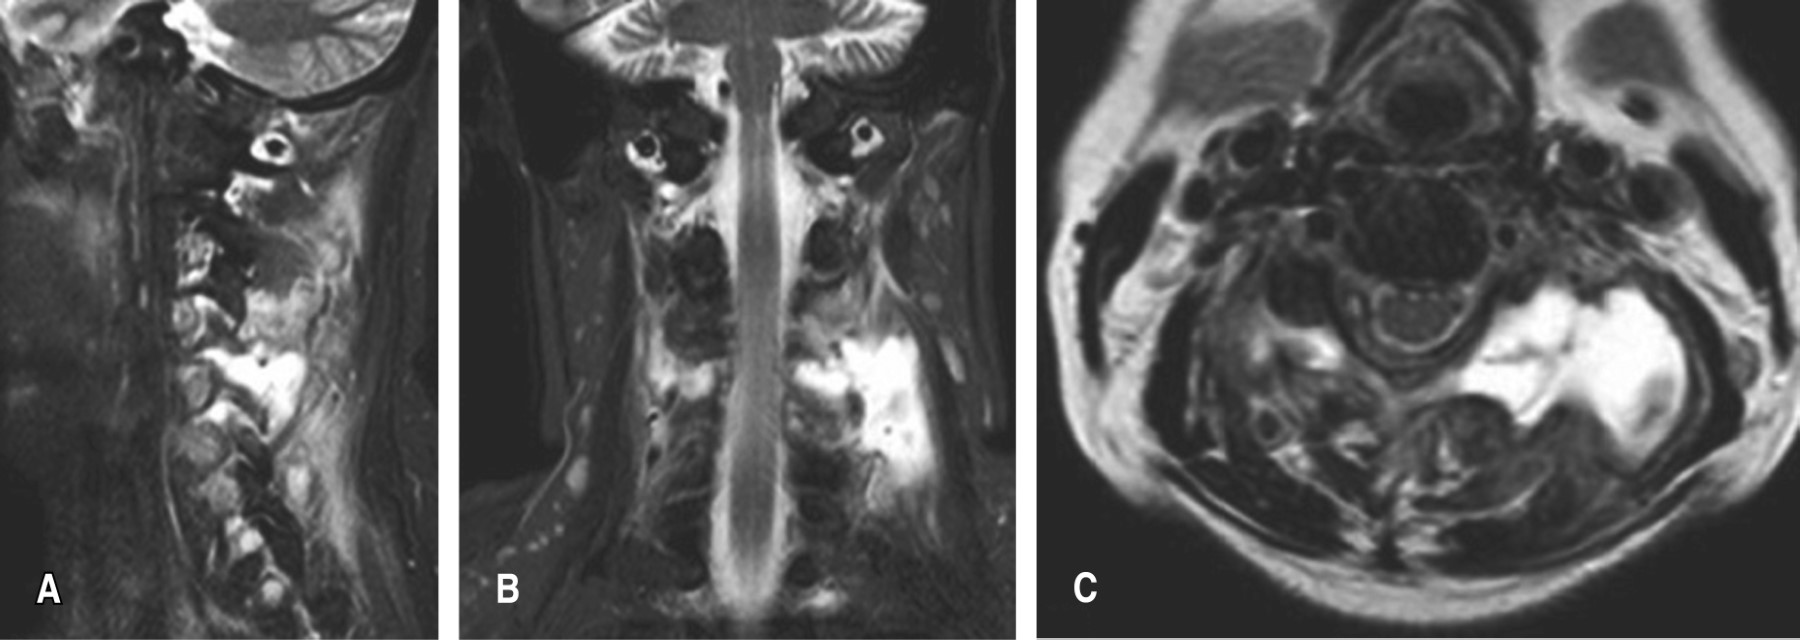

La resonancia magnética nuclear muestra en secuencia T2 en corte sagital una imagen hiperintensa a nivel paravertebral izquierda de C4-C5 coincidente con colección líquida, con aparente compromiso de articulación facetaria, el cual se corrobora en el corte axial de la misma secuencia (Figura 2).